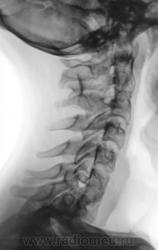

Подросток направлен в рентгеновский кабинет с диагнозом "сколиоз"...

Сколиоз-то сколиоз, но генеза "аномального".

Это синостоз тел верхних шейных позвонков и С6-С7? И боковые клиновидные полупозвонки в верхнегрудном отделе? Это синдром Клиппеля-Файля? А может и Шпренгеля...